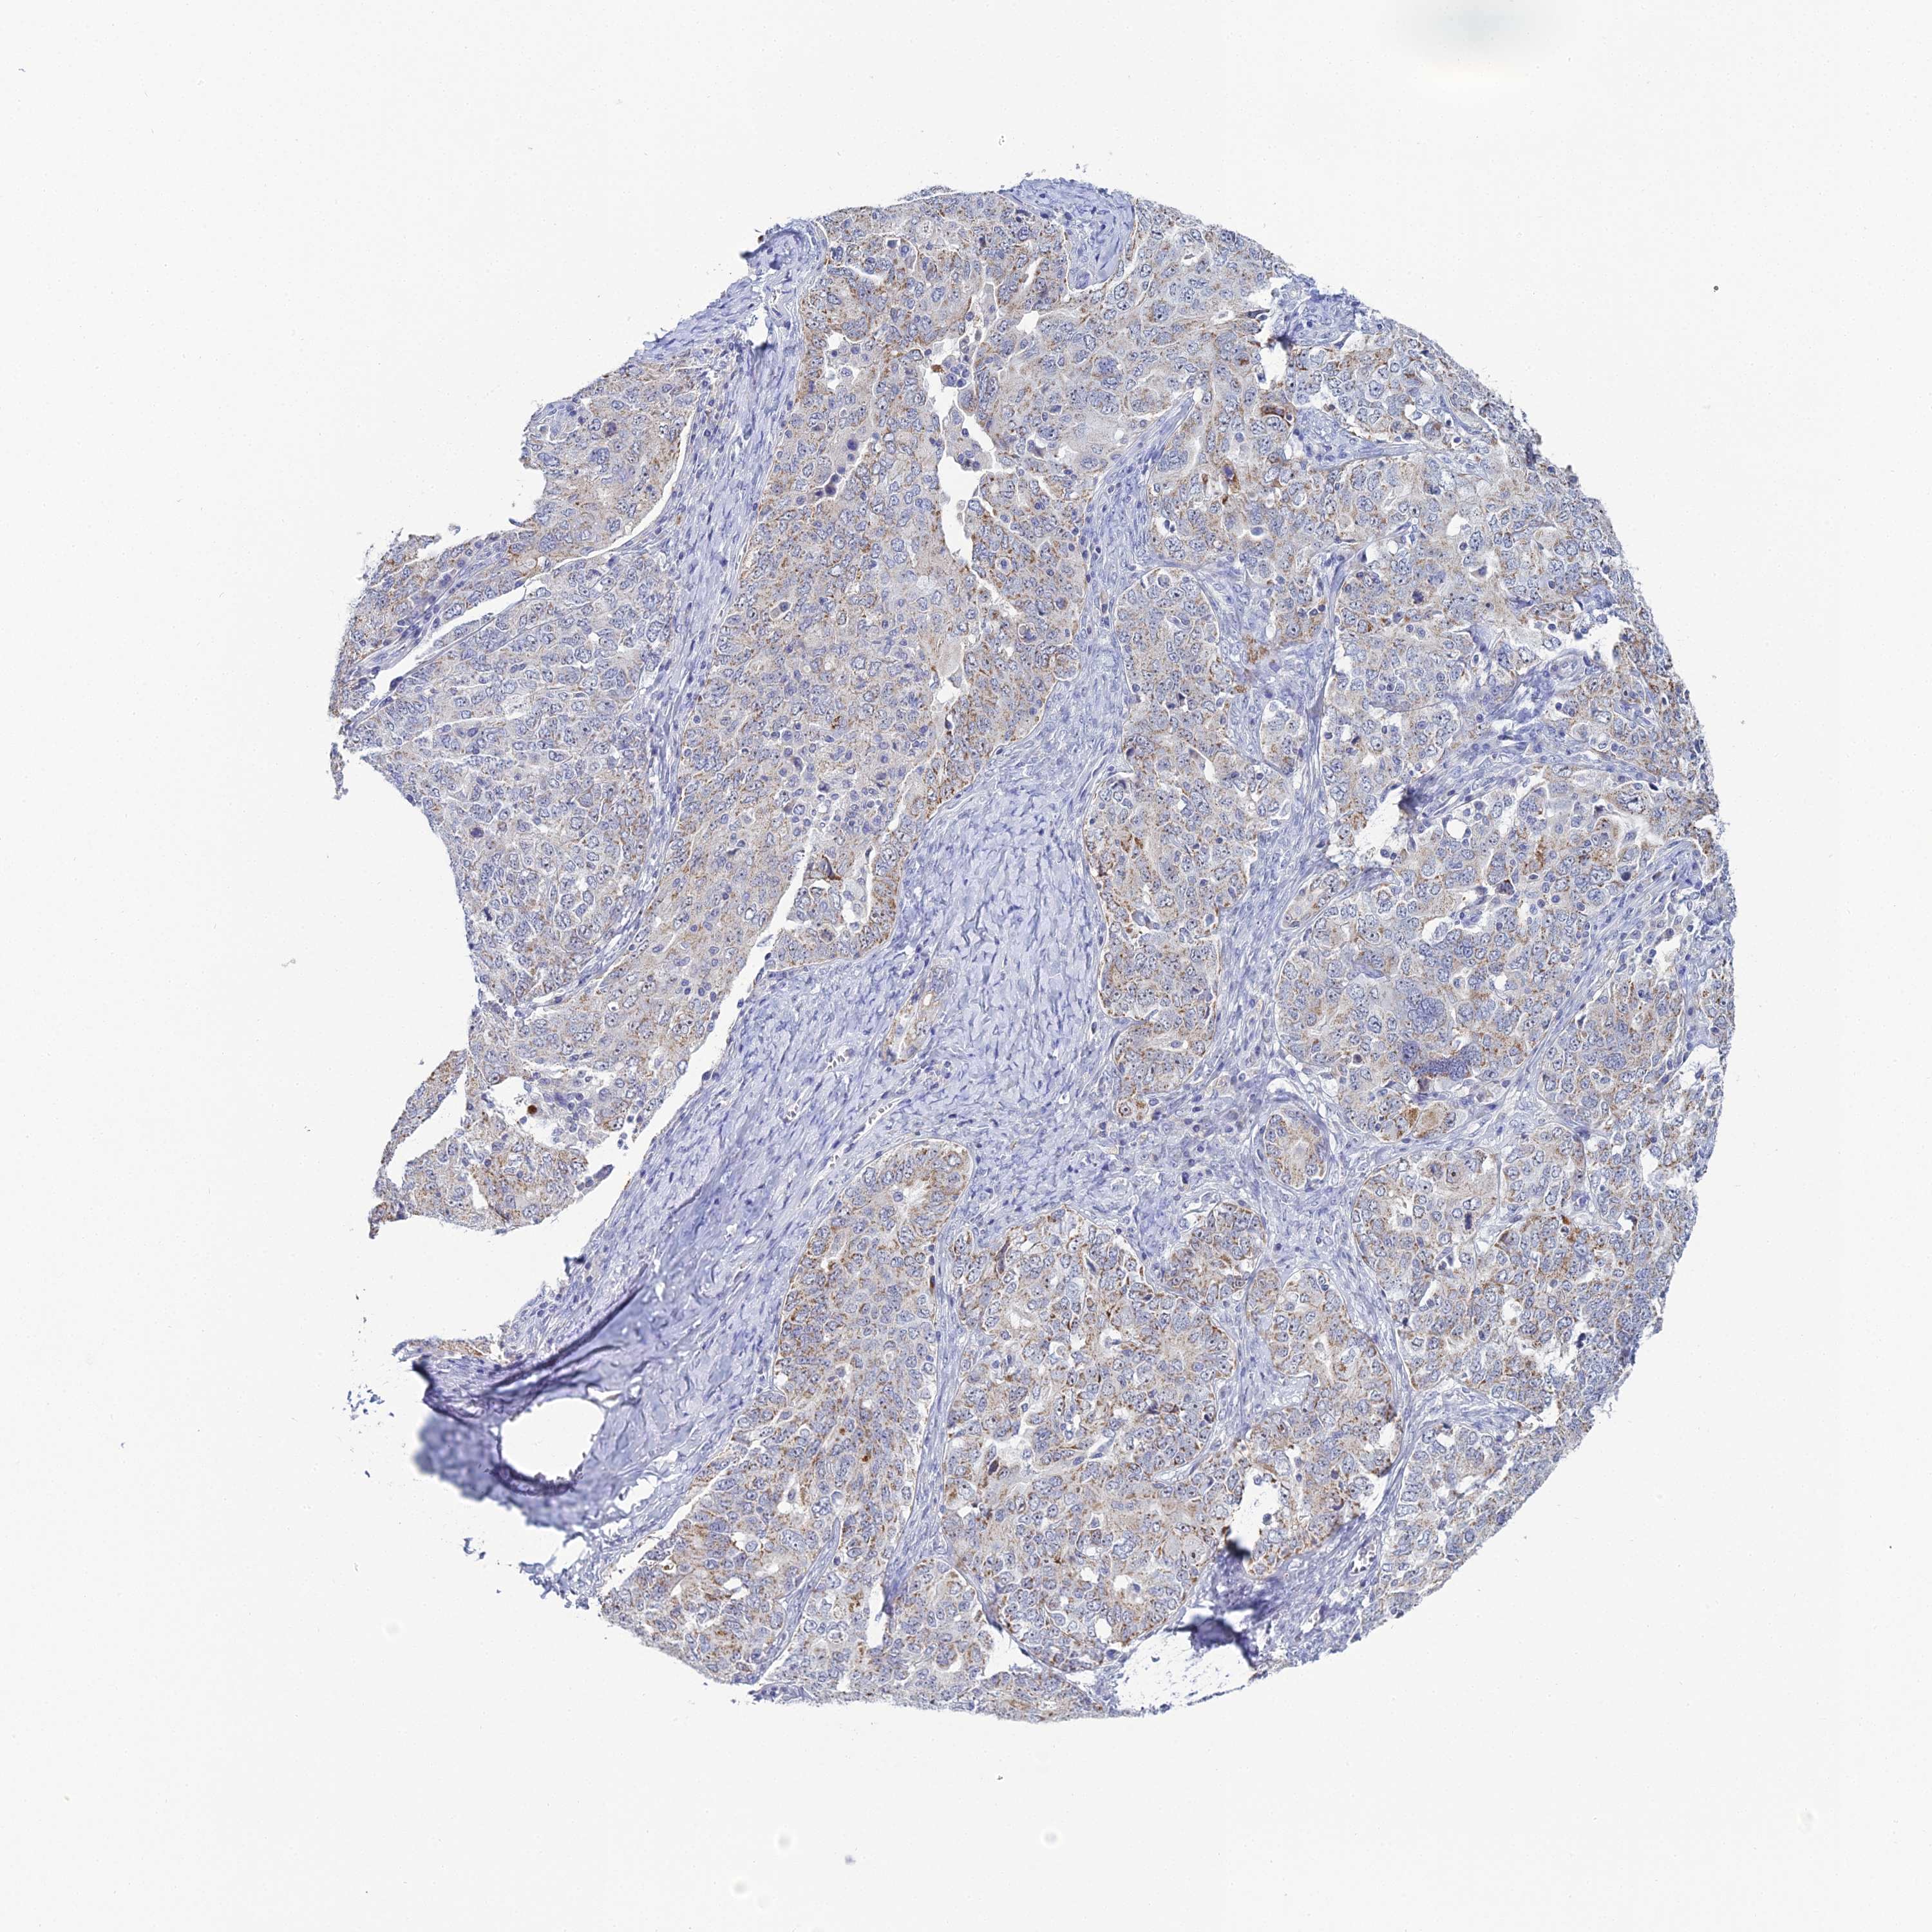

OVARIAN CANCER - Protein expressioni

A mouse-over function shows sample information and annotation data. Click on an image to view it in a full screen mode. Samples can be filtered based on level of antibody staining by selecting one or several of the following categories: high, medium, low and not detected. The assay and annotation is described here.

Note that samples used for immunohistochemistry by the Human Protein Atlas do not correspond to samples in the TCGA dataset.

Antibody stainingi

Antibody staining in the annotated cell types in the current human tissue is reported as not detected, low, medium, or high, based on conventional immunohistochemistry profiling in selected tissues. This score is based on the combination of the staining intensity and fraction of stained cells.

Each image is clickable and will lead to virtual microscopy that enables deeper exploration of all samples and also displays staining intensity scores, fraction scores and subcellular localization as well as patient and tissue information for each sample.

Antibody HPA045188

Staining

High

Medium

Low

Not detected

Intensity

Strong

Moderate

Weak

Negative

Quantity

>75%

75%-25%

<25%

None

Location

Nuclear

Cytoplasmic/membranous

Cytoplasmic/membranous,nuclear

Cystadenocarcinoma, serous, NOS

Carcinoma, endometroid

Cystadenocarcinoma, mucinous, NOS

Carcinoma, NOS